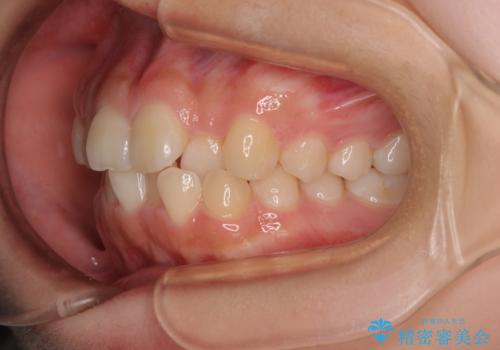

- 前歯のクロスバイトと口元の膨らんだ横顔の印象を気にして来院された患者様です。

レントゲン写真の分析結果からは、それほど口元が突出しているという結果にはなりませんでした。

しかしながら、唇を閉じたときに口元に緊張感があり、そのまま叢生を解消すると横顔が突出した印象になる可能性が高かったため、上下左右の小臼歯4本を抜歯して、ワイヤー装置にて矯正治療を行うこととしました。